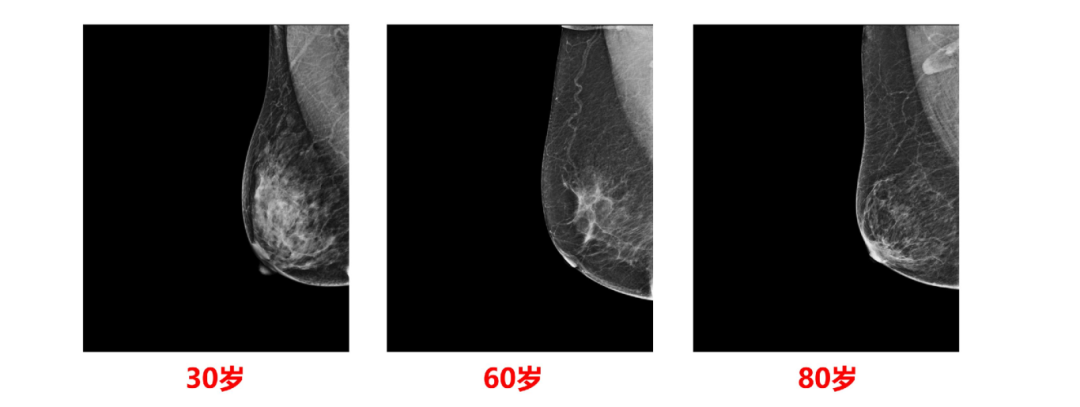

在女性的一生中,30岁前后的青壮年时期,腺体丰富犹如树叶枝繁叶 茂一般。到50更年期前后,由于卵巢分泌激素的减少,腺体开始出现退化萎缩,犹如树叶凋零一般。到老年女性,腺体萎缩明显,大部分腺体转化为脂肪组织。乳房内腺体的萎缩退化,在 X 线影像检查中体现得非常直观。